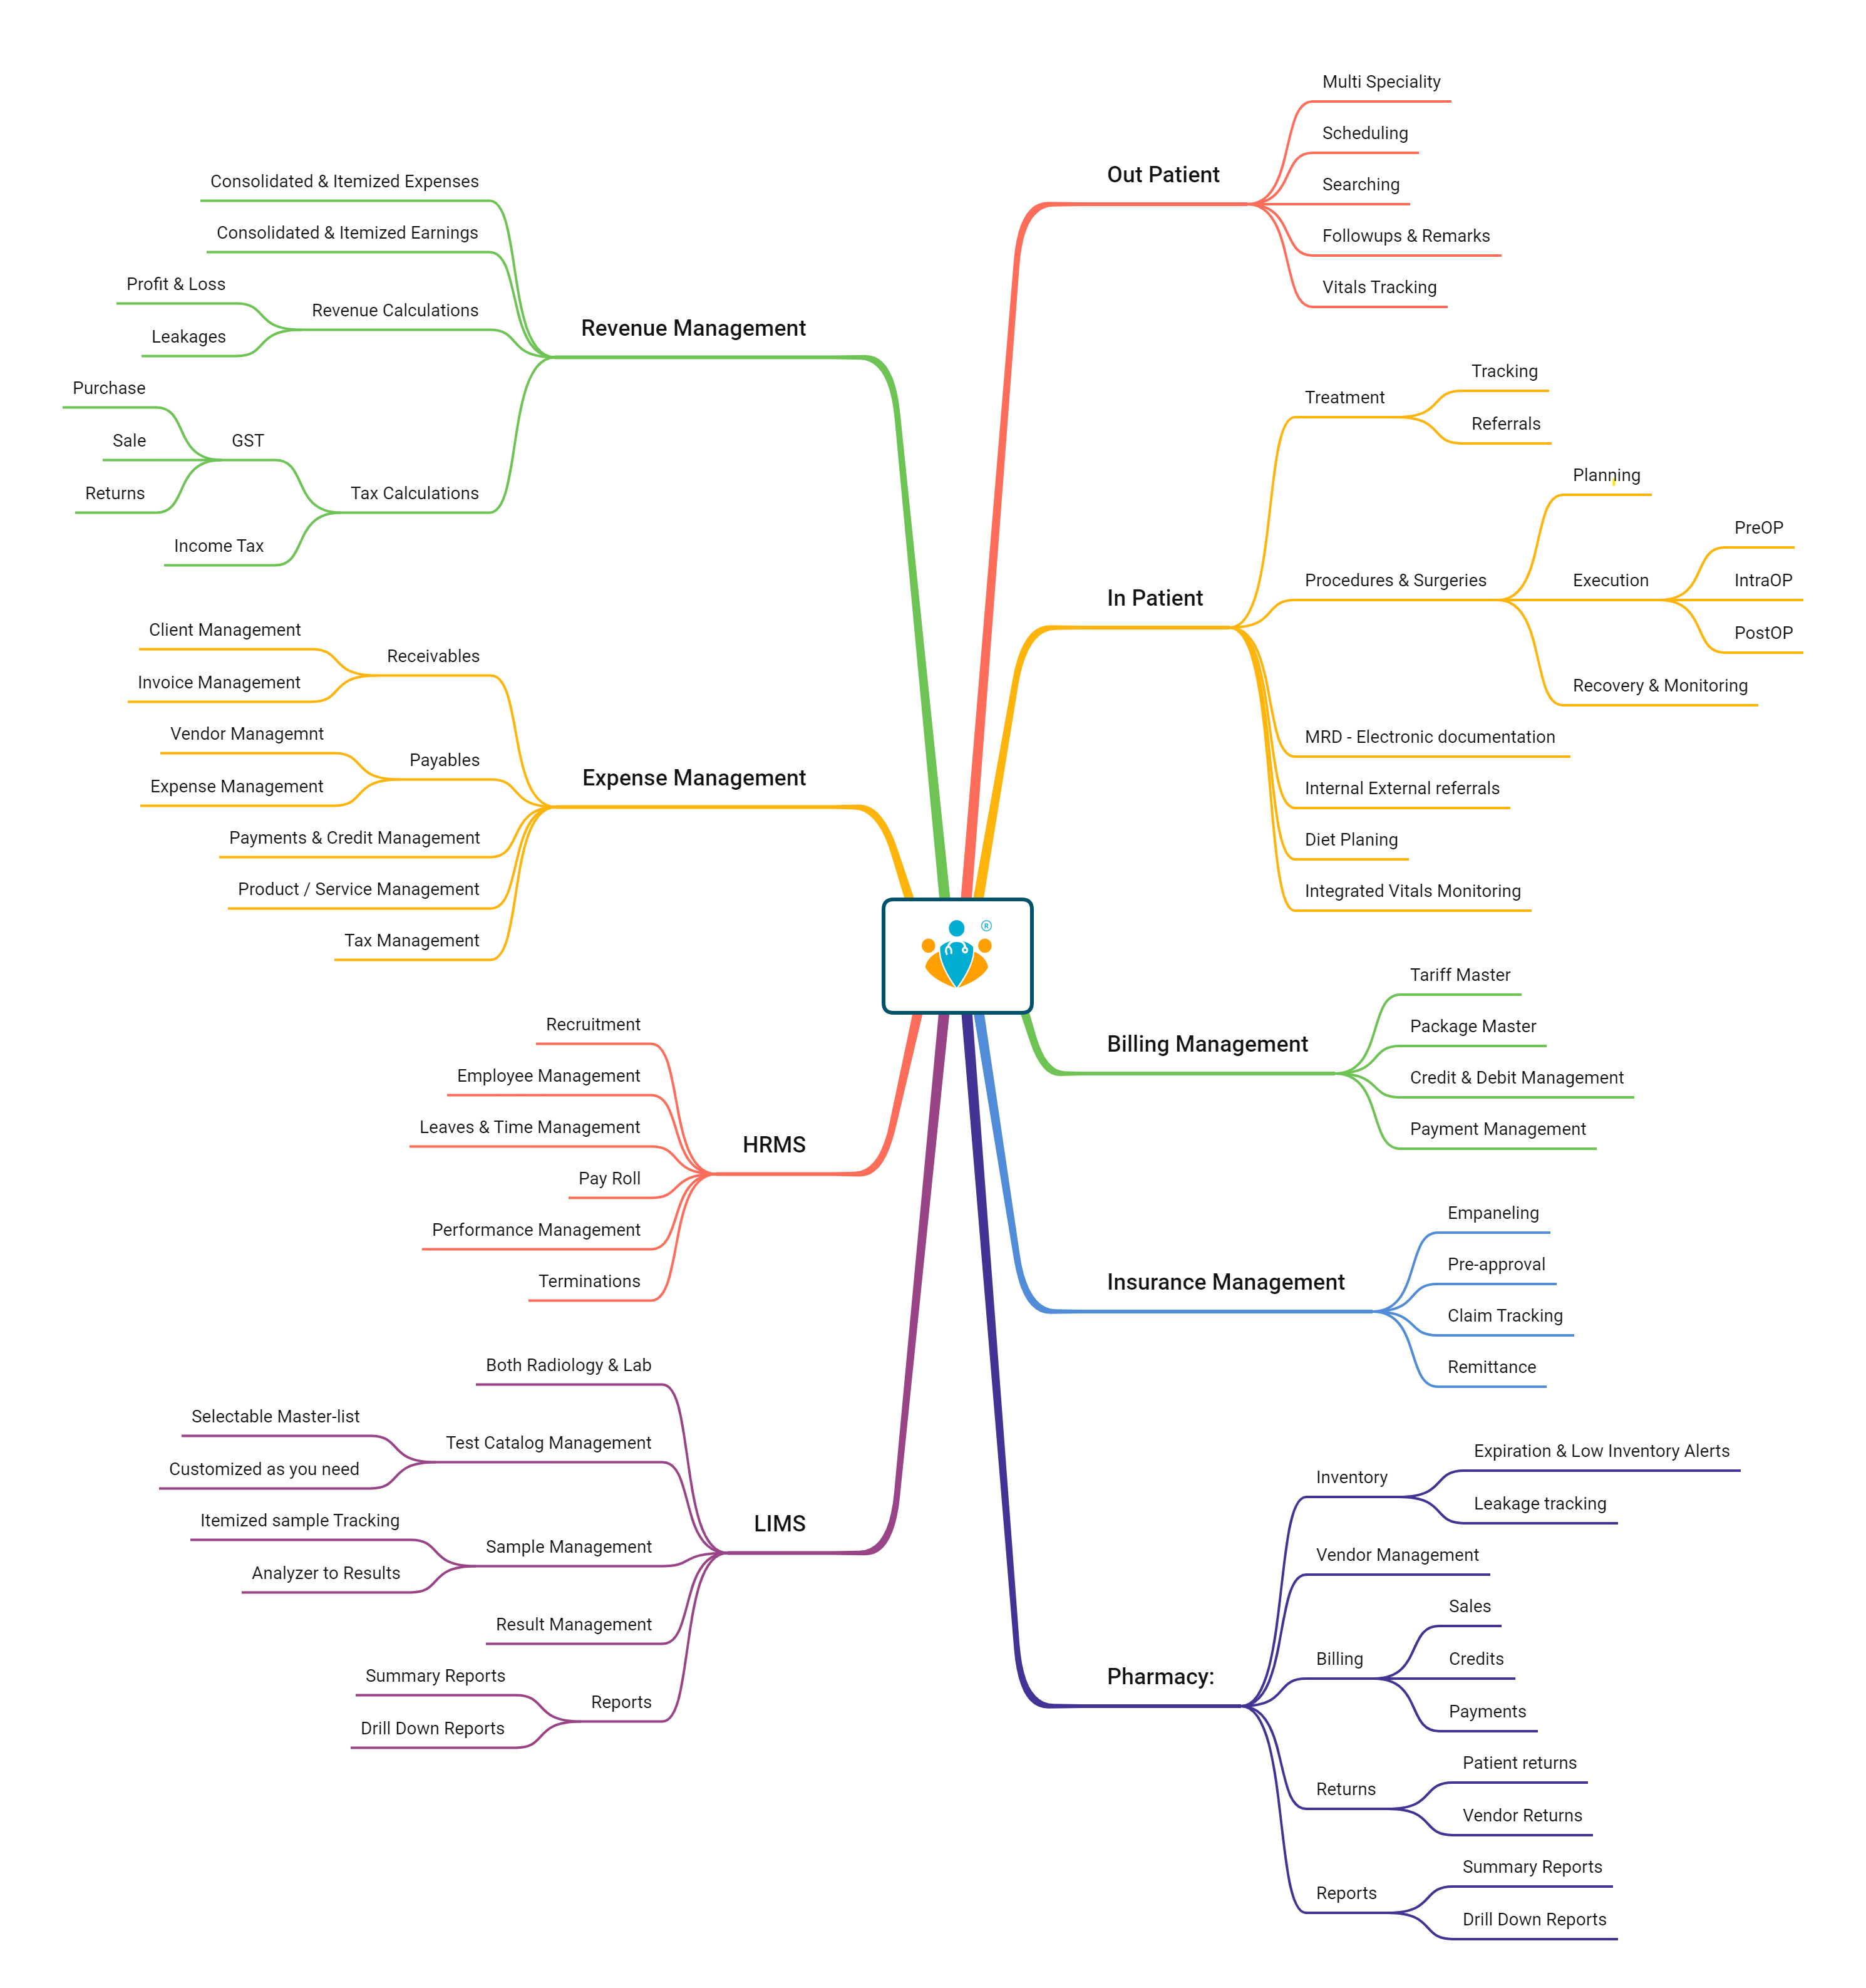

For Hospitals that provide in-patient services related to either a single-specialty or multiple specialties, TinyMedic's 'Hospital solution' offers comprehensive end-to-end workflow. From the moment a patient enters the emergency to in-patient treatment to medication delivery post-discharge, We provide you with simple & intuitive features.

Our integrated Pharmacy & Laboratory modules seamlessly unify your organization's workflows for efficiency, accuracy, and patient-centric service. Further, the TinyMedic platform provides you with features that help track your patient's health post-discharge.

All of the interactions with the patients are auto-synced to the hospital's medical records and the patient's PHRs. We help you handle your OP & IP investigations quickly and comprehensively with our specialty EHR, e-prescriptions, and real-time communication between all the departments in your organization. IP investigation or an OP investigation, Our cloud-based solution is integrated with the patient's application for consistent and streamlined medication management.

TinyMedic's comprehensive Pharmacy Management solution offers end-to-end features - Prescription Processing, Billing, Payments, Inventory, Stock Auditing, Accounting, Analytics, and Reporting.

TinyMedic's comprehensive Lab Management solution offers end-to-end features - Investigation Prescription, Billing, Payments, RIS/PACS, Stock Auditing, Accounting, Analytics, and Reporting.

Depending on the services you offer to the patients - OP, IP, in-house Diagnostic Lab & Pharmacy- We cater to your specific needs through our modular solutions to minimize costs for you. TinyMedic offers Modular solutions to cater to independent Pharmacies, Pharmacy Distributors, Labs, Single Speciality Clinics, Multi-speciality hospitals, and chains of Multi-speciality hospitals looking to improve their efficiency and enhance patient engagement.

Hospitals, Clinics, Labs, and pharmacies play different roles in healthcare delivery. Each interacts differently with the patients and hence needs unique features to cater to the needs of the patients. TinyMedic's Modular solution provides specific features for each entity while allowing hospitals, labs, and pharmacies to integrate seamlessly to serve patients through one unified platform. By integrating our modules into a single system, hospitals, labs, and pharmacies can reduce costs while improving patient care.

Additionally, an integrated platform like TinyMedic makes it easier for healthcare professionals to access and manage data from multiple sources quickly and efficiently. For example, Our Hospital Module can manage patient records, billing, scheduling, and other administrative tasks. Similarly, Our Lab Module can track laboratory tests and results, while our Pharmacy Module can help pharmacies manage their inventory and orders.